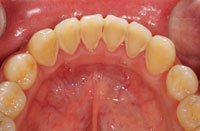

また、お口の中の状態をよりよく知るために、口腔内写真も撮ります。

(3)歯周組織検査・2回目

歯周ポケット(歯と歯ぐきの間)の深さや、出血、歯が動いていないかなどを調べます。

![]()